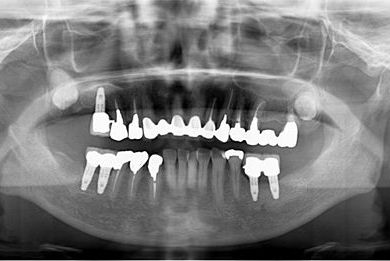

治療前

• 治療前